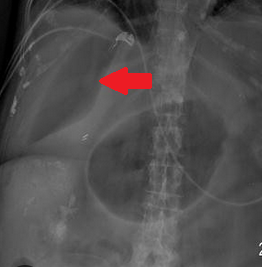

Απλή ακτινογραφία κοιλίας. Σημείο υπερδιαυγαστικού ήπατος (Ευγενική παραχώρηση Dr. V. Penopoulos)